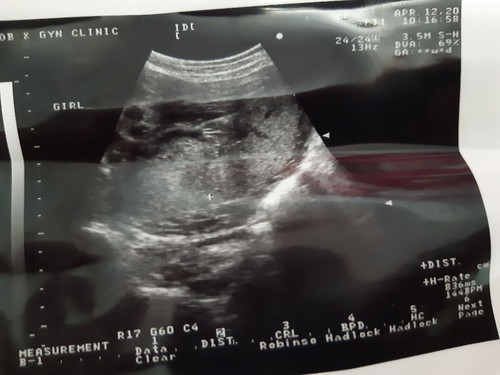

พอดีแม่ไปอัลเตอร์ซาวเพศลูกมา หมอบอกเห็น 3 ขีด หมอบอกเป็น ผู้หญิง แม่ๆคิดว่าอย่างไรกันบ่างค่ะ

คงใช่อย่างที่หมอว่าค่ะ 👧 หมอคงมั่นใจเลยเขียนมาให้ด้วยเลย